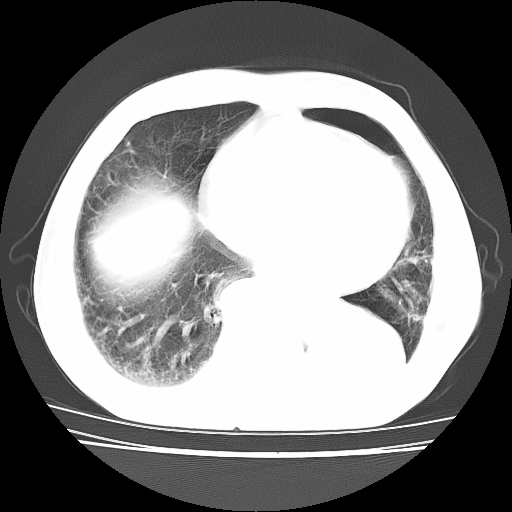

男,71岁,咳嗽,气喘10年,再发并咯血.胸片见气胸

考虑  左肺中心型肺癌伴阻塞性肺炎,肺不张,纵膈淋巴结肿大。慢支炎,肺气肿,左侧气胸肺压缩5%

左侧中央型肺癌伴纵膈淋巴结转移。

左肺中心型肺癌伴阻塞性肺炎,肺不张,纵膈淋巴结肿大

1)考虑左肺中心型肺癌伴阻塞性肺炎、左肺下叶肺不张、左侧肺气肿,纵膈淋巴结转移。2)左侧气胸(肺组织压缩约5%)。

左肺中心型肺癌伴阻塞性肺不张、肺气肿 。

1)考虑左肺中心型肺癌伴阻塞性肺炎、左肺下叶肺不张、左侧肺气肿,纵膈淋巴结转移。2)左侧气胸。